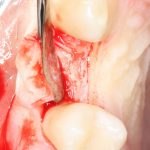

Наложение швов.

Помните, в самом начале операции мы планировали наложение швов с учётом будущего вестибулярного смещения лоскута? Так вот, теперь у нас есть возможность не просто сместить, но и зафиксировать вестибулярный лоскут. Делается это, так сказать, с подворотом края снаружи:

Обратите снимание, что альвеолярный отросток в этой области стал более объемным. Этого удалось добиться без всяких остеопластических операций или гингивопластики, путём простого перемещения тканей.